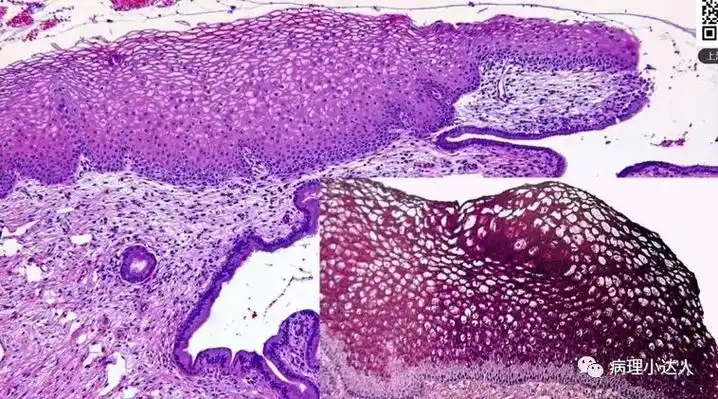

宫颈鳞状上皮病变

低级别鳞状上皮内病变(low-grade squamous intraepithelial lesion

学习笔记低级别鳞状上皮内病变的诊断与鉴别诊断

【学习笔记】低级别鳞状上皮内病变的诊断与鉴别诊断